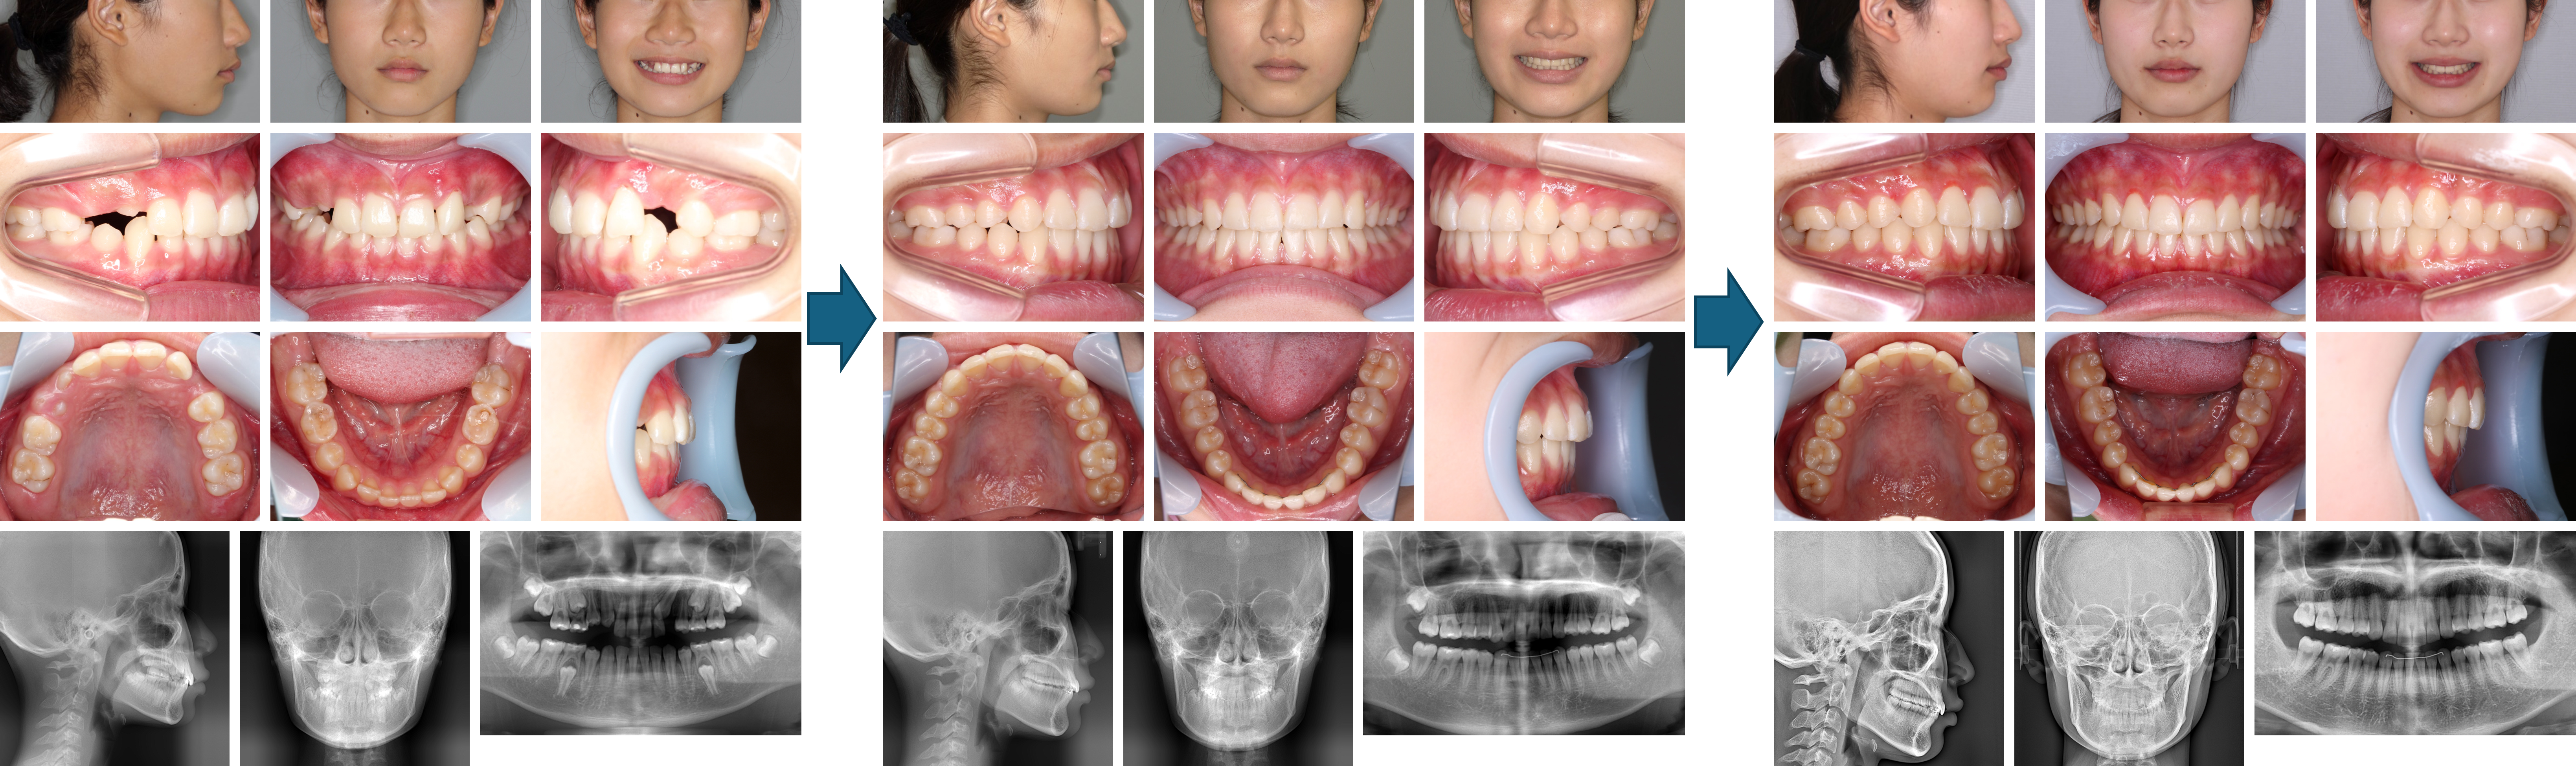

【治療例 K7719】初診時年齢:12歳1か月 / 性別:男性 / 主訴:出っ歯で口が閉じにくい

症例の概要:主訴は出っ歯で口が閉じにくい。サービカルヘッドギアと2×4装置にて上顎骨の成長抑制、下顎の成長促進を行った。さらにマルチブラケット装置にて緊密な咬合を獲得し、好ましい側貌を得ることが出来た。

主訴: 出っ歯で口が閉じにくい

診断名: 上顎前歯が唇側傾斜した上顎前突症例

使用した主な装置: マルチブラケット装置、サービカルヘットギア、歯肉切除

抜歯/非抜歯および抜歯部位: 非抜歯

治療期間:2年5か月

治療回数:25回